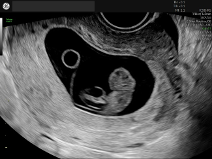

- Optimiser le suivi obstétrical : réaliser une datation de grossesse plus fiable est essentiel pour conditionner l’efficacité du suivi de vos patientes [5].

- Simplicité et fiabilité : il offre une qualité d’image 2D fiable sans complexité inutile.

Sa philosophie est claire ! Aller à l’essentiel, avec un échographe simple à prendre en main, pensé pour un usage quotidien, accessible et rassurant pour démarrer.